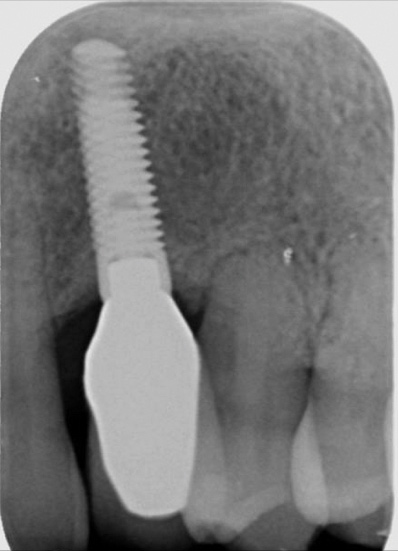

The first step in preventive strategies must be to perform a correct diagnosis of the peri-implant condition by accurately assessing the health of the peri-implant hard and soft tissues through periodontal probing and periapical radiographs at the time of definitive prosthetic installation. These measurements should be considered the baseline diagnosis and, therefore, represent a true starting point for evaluating the changes on the radiographic bone levels and probing pocket depths (PPD) at future recall appointments (Figure 1 and Figure 2).6 Although probing depth measurements of peri-implant tissues do not have the same diagnostic value as probing periodontal tissues, there is evidence that BOP is the most objective sign of peri-implant tissue inflammation; significant deepening of PPD compared with baseline measurements is also a sign of disease that indicates the need to perform a radiographic evaluation (Figure 3 through Figure 5).6,10,11

Fig 1. Baseline measurements at the time of prosthetic delivery: probing pocket depth and

Figure 1

Fig 2. periapical radiographs.

Figure 2